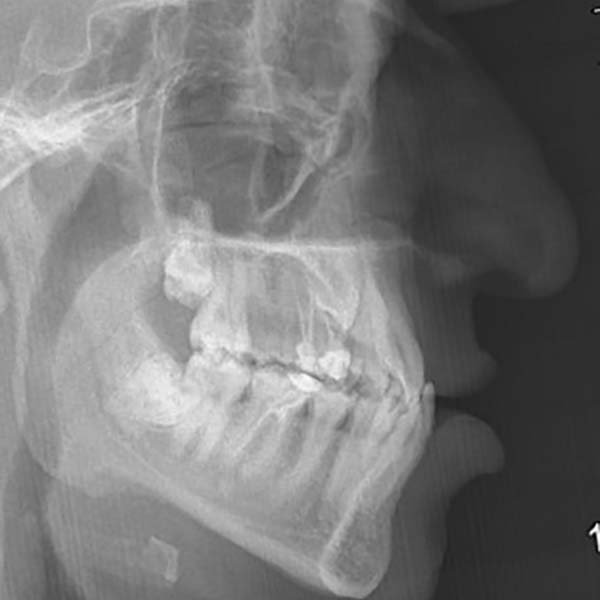

My young friend visited me suffering from a complete Bite collapse, a severe anterior crossbite, in addition to the loss of many of his back teeth. He was so frustrated, thinking that his case is incurable, and this frustration was reflected on his shy smile.

After examining the case, I have conveyed the good news to our friend, that despite the difficulty of his case, we were able to reach a satisfying result through orthodontic treatment. As expected, tooth extraction was nessecary, to open space for the rest of his teeth to arrange and treat the anterior crossbite. At the end of the treatment, most of our friend’s dental problems were treated, and he could smile happily and with confidence.